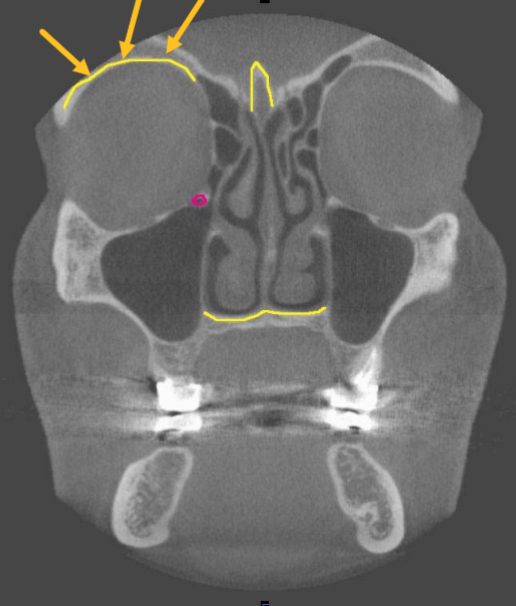

orbital roof

what are the arrows pointing to

maxillary sinus

what is indicated by the GREEN dot

orbit

identify the structure